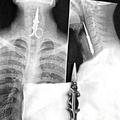

Boleča izkušnja Ponesreči pogoltnil škarje Kitajcu Kong Linu je bilo zagotovo žal, da ni poslušal nasvetov matere, ki mu je v mladosti verjetno kdaj omenila, da s…